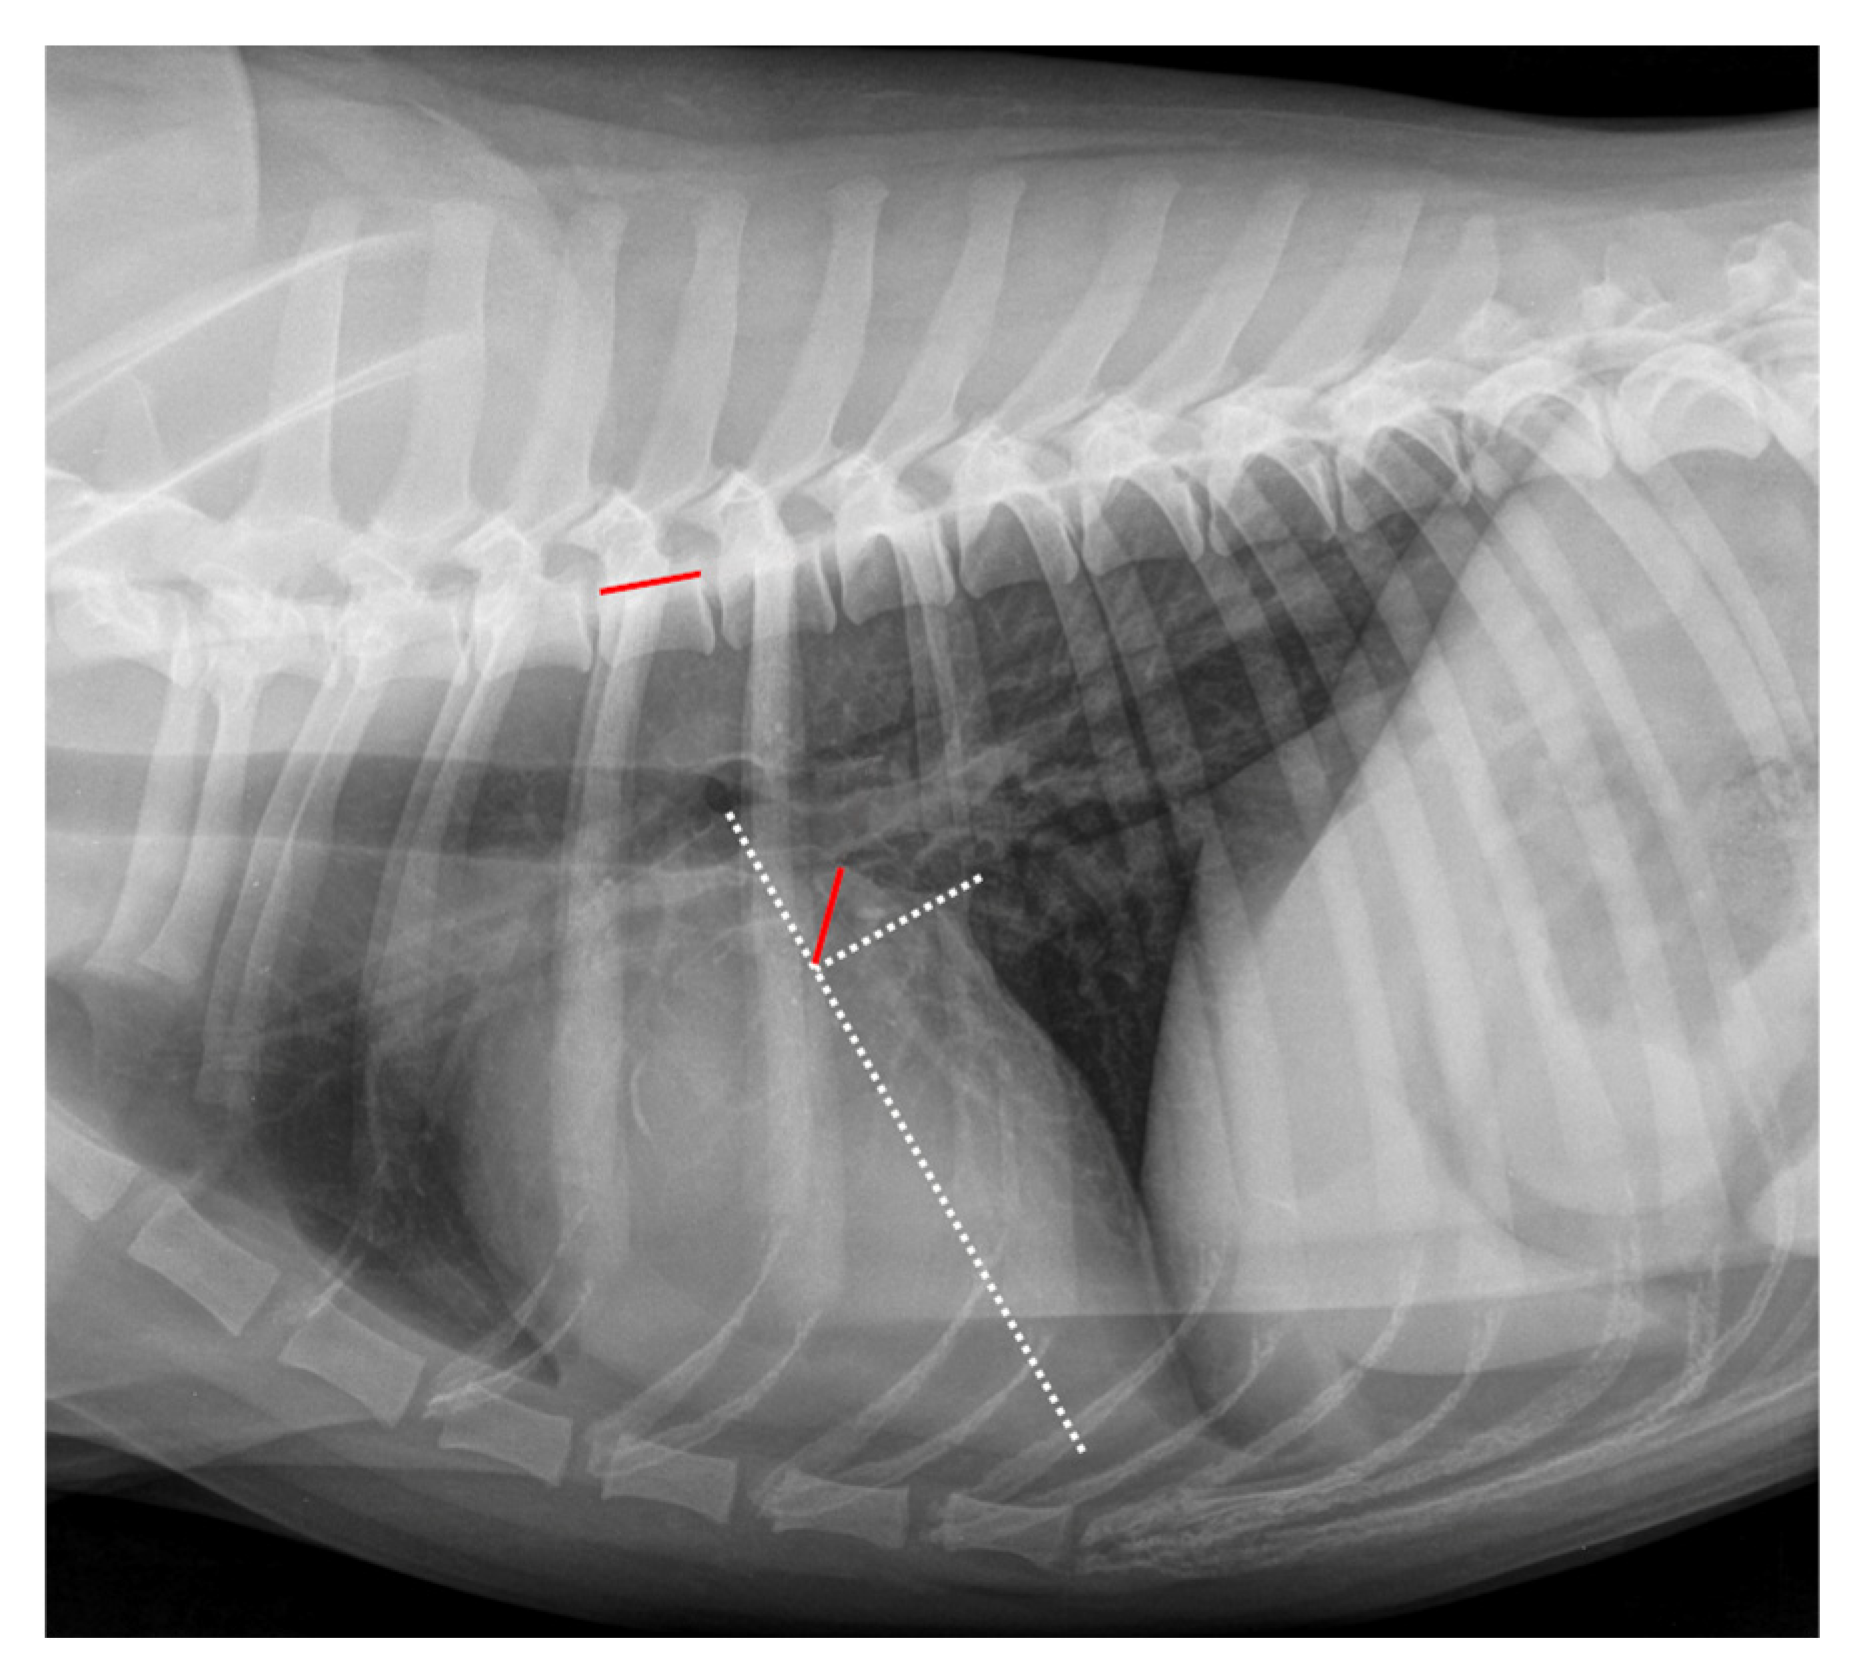

Error in Figure 2